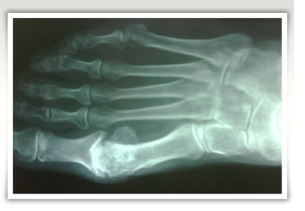

El médico generalmente puede diagnosticar este problema examinándole el pie. Se puede

tomar una radiografía del pie para descartar problemas óseos. Con una resonancia

magnética o una ecografía de alta resolución, se puede diagnosticar con éxito el neuroma de

Morton.